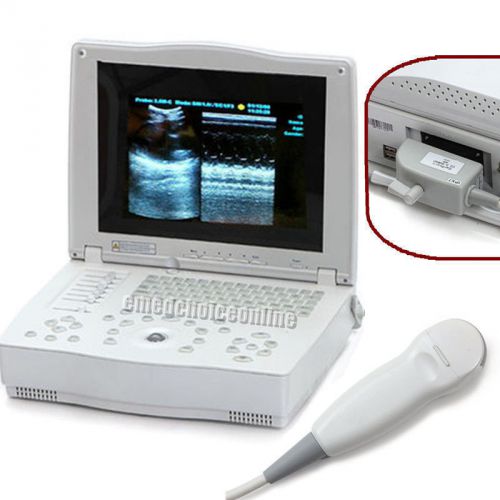

FDA Full Digital Laptop 15-inch Ultrasound Scanner +Convex Probe + Free 3D CE

FULL DIGITAL LAPTOP ULTRASOUND SCANNER MACHINE + CONVEX PROBE CE 100% WARRANTY